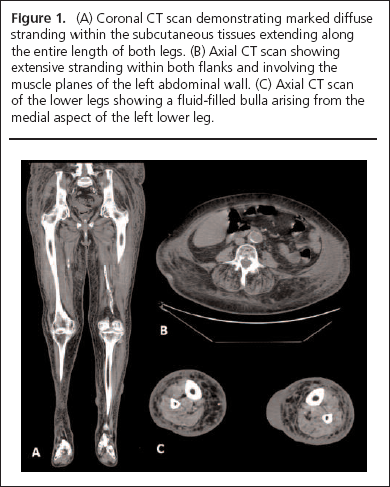

An emergency CT scan demonstrated marked diffuse stranding within the fat subcutaneously and within muscle planes, particularly affecting the left flank but extending along the entire length of both legs. Multiple fluid-filled bullae were seen in the distal left leg (Figure 1).

Biscoe-figure1